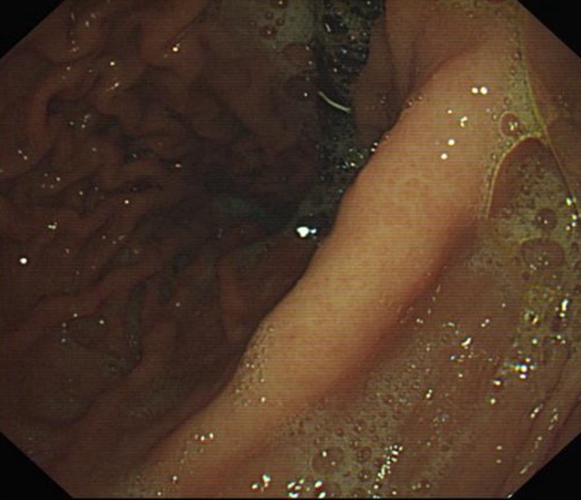

急性胃炎圖片

急性胃炎

急性胃炎胃部